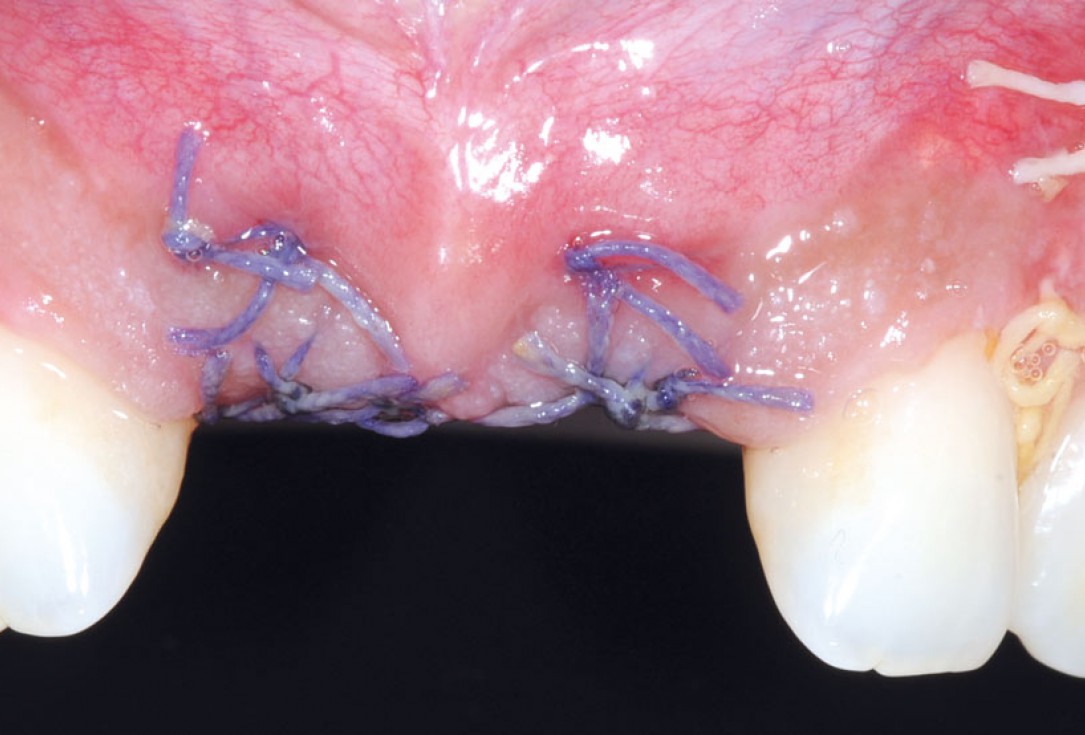

19/26 - 3 weeks post-op: eventless healingBone augmentation in aesthetic zone with maxgraft® bonering - Dr. A. Patel

20/26 - 6 weeks post-op: sutures were removedBone augmentation in aesthetic zone with maxgraft® bonering - Dr. A. Patel